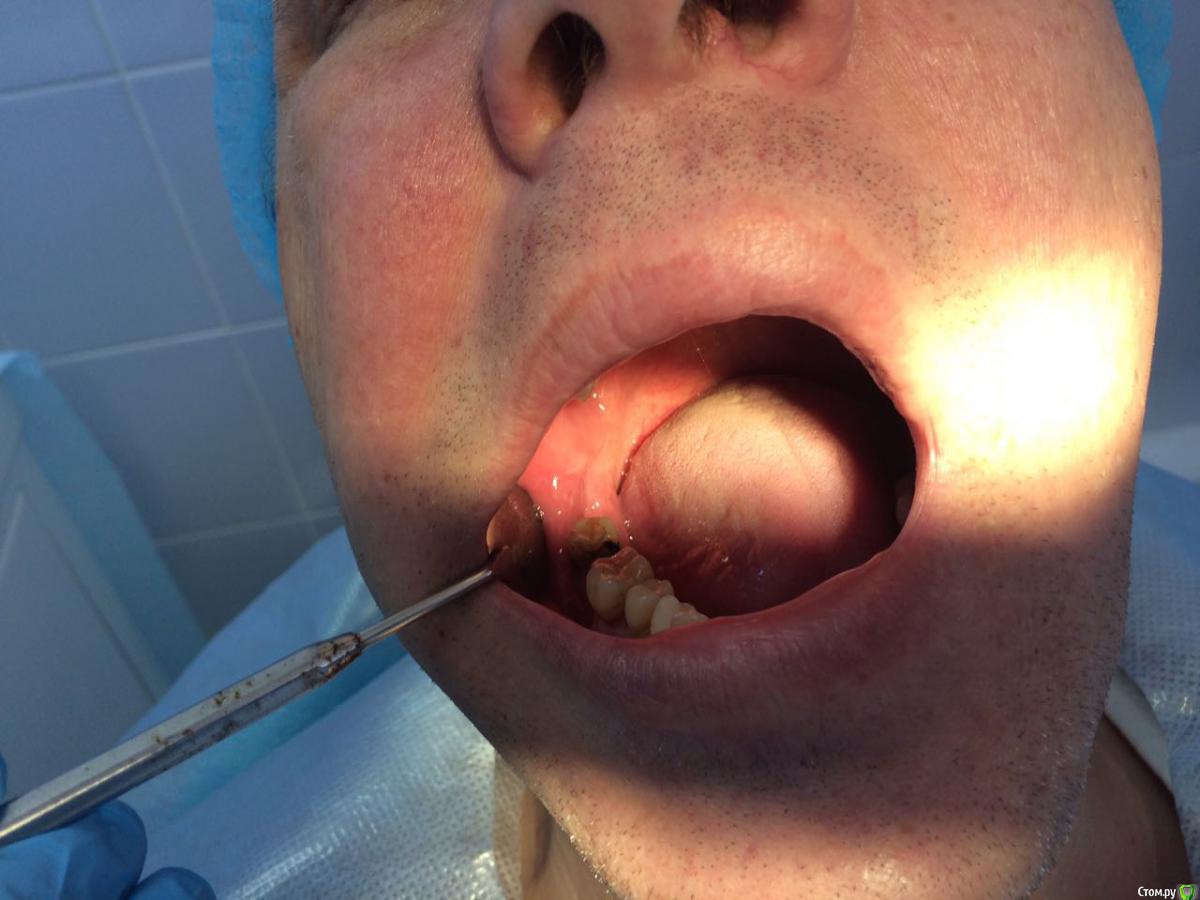

Пациент с жалобами на отсутствие 47 разрушение 46,48. После совещания с ортопедом и терапевтом принято решение удалять 46,48 и устанавливать импланты в позицию 46,47. post-48560-0-74269200-1490419709_thumb.jpgpost-48560-0-43642200-1490419772_thumb.jpgПрисутствует парадонтоз, лечение у пародонтолога прошел заранее. Решено было 46 ставить одномоментно, с графтом и мембранкой, 47 по стандартному протоколу, импланты alpha bio aic 4,2*12, 4,2*10 соответственно. post-48560-0-27512000-1490420040_thumb.jpgpost-48560-0-53003700-1490420066_thumb.jpg Сначала удалил, атравматично с распилом по бифуркации.post-48560-0-43340000-1490420143_thumb.jpgpost-48560-0-35881400-1490420170_thumb.jpgРаскрылся над 47, подготовил ложе, пины параллельности. Здесь вопрос, думаю зря широко отслоился и затронул 46?post-48560-0-32979400-1490420293_thumb.jpgpost-48560-0-94312700-1490420324_thumb.jpgустановка имплантов с фдм, графт в лунки 46 апатос, мембрана Эва. Снять не получилось. Нить моно 5-0. Тут опять вопрос фдм нужно было ставить шире? Но опять же импланты заглубил немного...post-48560-0-50977700-1490420493_thumb.jpg и контрольный. Конструктивная критика приветствуется)))